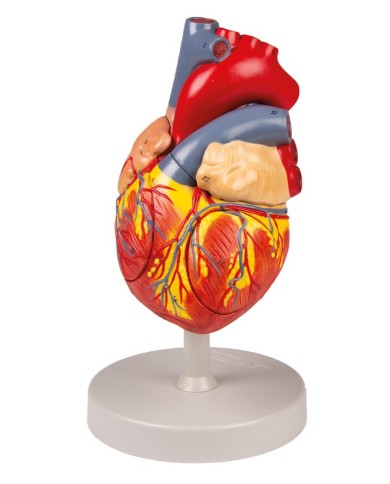

Modello di cuore di alta qualità scomponibile in 5 parti

Modello di cuore di alta qualità scomponibile in 5 parti

Modello anatomico di cuore, ingrandito 2 volte, su cavalletto

Questo modello dettagliato mostra, oltre alle strutture anatomiche del cuore, anche una parte del diaframma (base)

Realizzato in stampa 3D ad elevatissima risoluzione a colori.